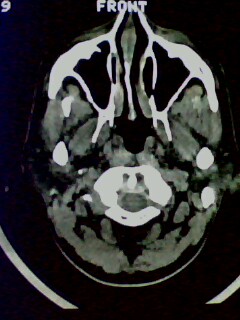

以下是引用随光逐影在2009-5-20 19:22:00的发言:[br]1)考虑左上颌骨近中线区含牙囊肿。2)鼻中隔右突偏曲。3)双侧下鼻甲肥大。